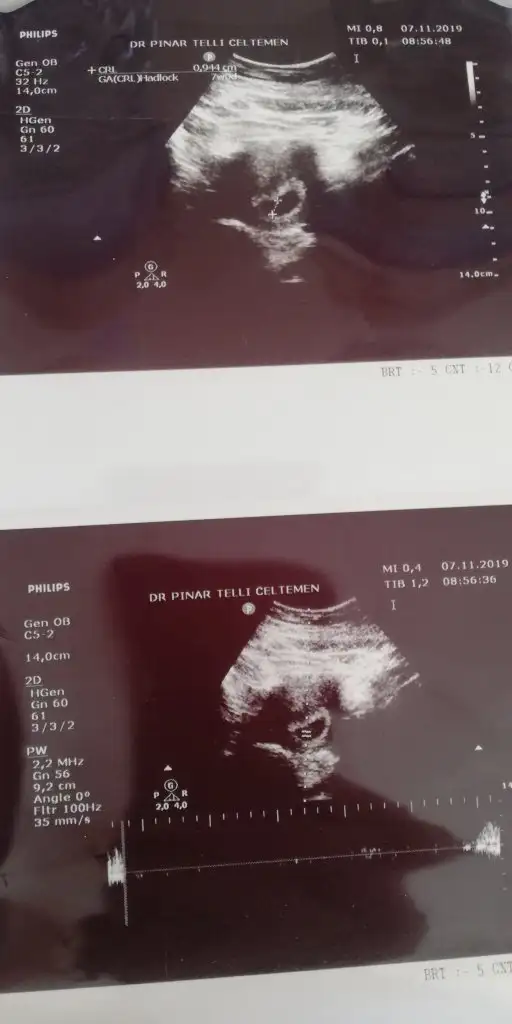

0.9 cm dedi doktor 😍

Eklentiler

• IMG_20191107_112610.webp

IMG_20191107_112610.webp

20,6 KB · Görüntüleme: 71